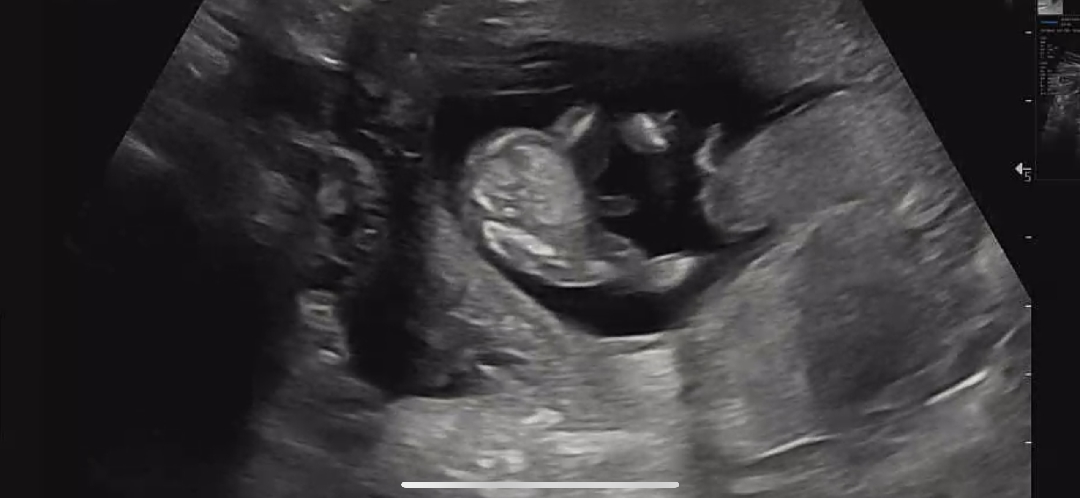

2주 뒤 초음파입니다 남자아기는 맞는 것 같네요

13주차 아기 꼬추

아기 꼬추가 이렇게 커요...?

굵기 보니까 탯줄 같은데요?? 고추는 끝이 뾰족해요 삼각점도 안보이구요 ㅎ

의사선생님이 빼박이라고 하셔서ㅋㅋㅋㅋ